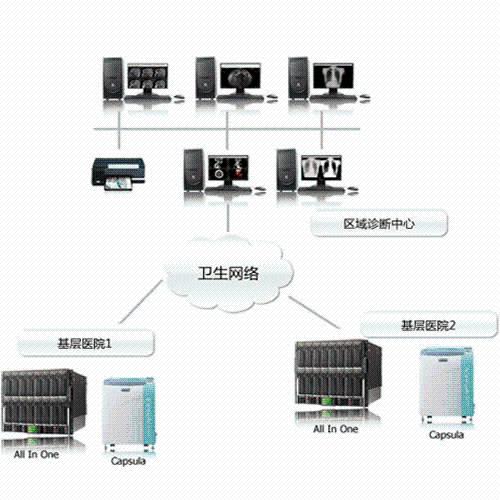

Directly access DICOM scans from/to your PACS

Works efficiently with patient’s DICOM scans from outside your organization

Load DICOM data directly from PACS, CD/DVD, USB, and local computer.

Upload DICOM data to your PACS directly from referral patient CD/DVD and local computer.

Easy to use patient search to locate patient data on your PACS.